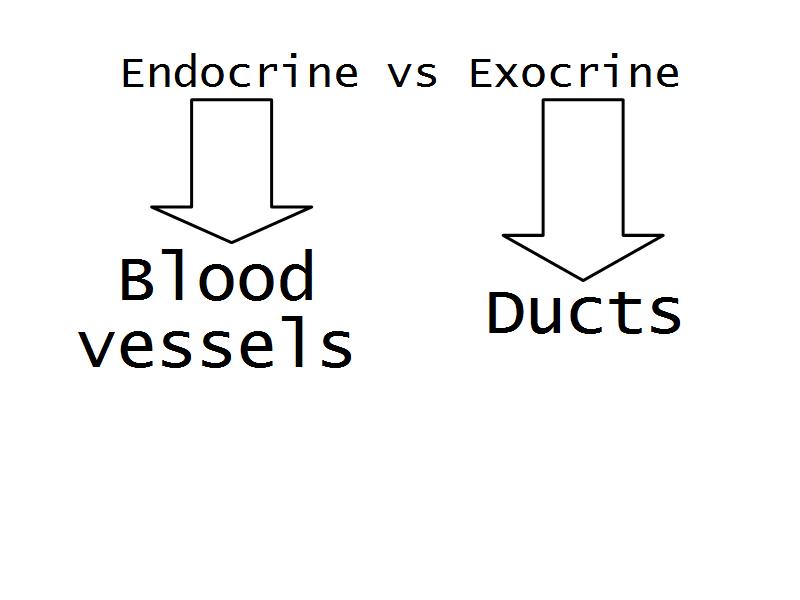

Name 10 endocrine organs

- Pituitary gland

- Thyroid gland

- Parathyroid glands

- Adrenal glands

- Pancreas

- Kidney

- Testis

- Ovary

- Corpus luteum

- Pineal gland